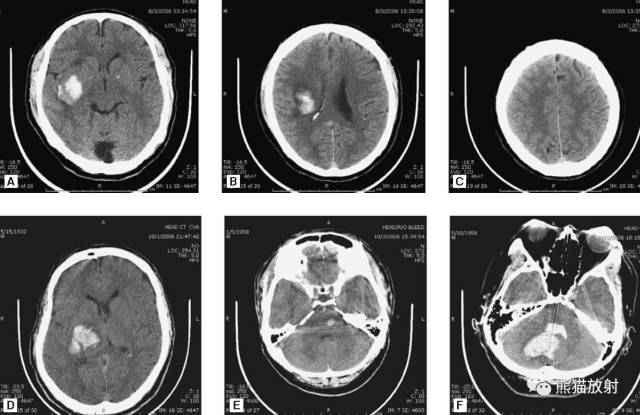

2、硬膜外血肿

硬膜外血肿、颅内积气(提示骨折)

硬膜外血肿(凸透镜样;可有或无颅骨骨折)。

3、硬膜下血肿

右侧硬膜下血肿(急性-高密度,慢性-低密度);右侧大脑水肿,中线结构移位。

(小脑幕下)硬膜下血肿

(大脑镰左侧)硬膜下血肿:可见轻度占位效应。

左侧硬膜下血肿:呈等密度,有占位效应,中线结构移位。

双侧亚急性硬膜下血肿:左侧可见急性出血,双侧占位效应平衡,中线结构无移位。

双侧等密度硬膜下血肿

4、蛛网膜下腔出血

外伤性蛛网膜下腔出血:脑沟、脑池内可见高密度影。

额叶及颞叶脑挫伤:脑出血并周围水肿,可随时间扩大,导致占位效应及脑疝。由于受周围骨质影响,脑基底部挫伤容易遗漏。

头部枪伤:可见*弹子**轨迹,穿越大脑中线,其毁灭性后果导致:侧脑室积血,蛛网膜下腔出血,脑积水(侧脑室颞角扩大),小脑幕疝(脑干周围基底池消失或不对称)。